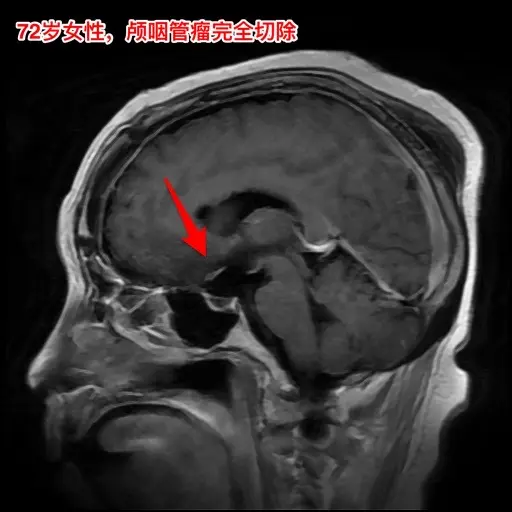

颅咽管瘤不单单是小孩子得的病!很多人认为颅咽管瘤是小孩子得的病,其实各个年龄段的人都可以患颅咽管瘤,我见过的颅咽管瘤病人年龄跨度从不到一岁到八十多岁! 相对而言,小孩子群体中(小于15岁)颅咽管瘤的发生率比较高! 这个72岁的山西晋城市老人在古稀之年患上了颅咽管瘤,病理报告是乳头型颅咽管瘤。10月25日在我科作了手术,11月13日出院。 老人在住院前胃肠功能不好,经常腹胀、消化不良。手术后也是经常感觉腹胀、食欲不振,身体康复过程相对比较缓慢。 老年人一般来说都伴有老年性疾病,比如糖尿病、高血压病、高脂血症、动脉硬化,身体大脏器机能下降,所以老年人患颅咽管瘤,作手术后恢复会比较慢,出意外的风险会增加,尤其是血管方面的并发症会增加,比如深静脉血栓、心肌梗死等。